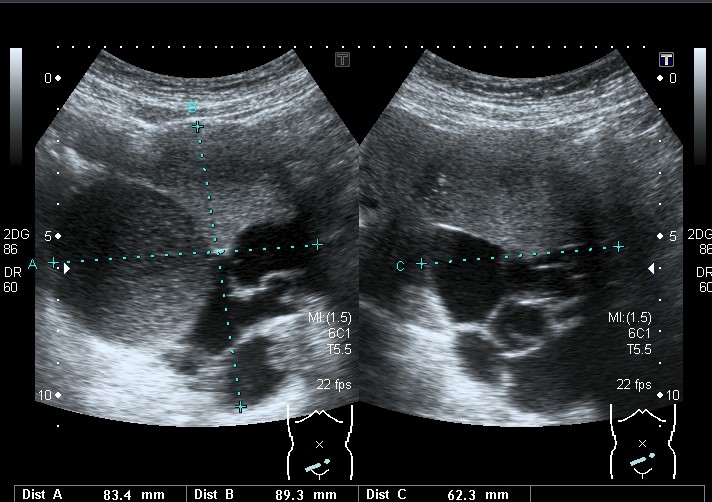

嚢胞性湿腫は、リンパ系の閉塞によって引き起こされる液体で満たされた嚢です。このシステムは、体内の液体の移動と白血球の輸送を助ける臓器と組織のネットワークです。嚢は通常、妊娠 9 週から 16 週の間に形成されます。

出生後に発生する嚢胞性湿潤腫は、赤ちゃんが生まれたときには気づかれない場合があります。それらは、子供が大きくなり、年齢が上がるにつれて目立つようになります。嚢胞性湿潤腫は通常、子供が2歳になるまでに現れます。

嚢胞性湿腫の主な症状は、柔らかい海綿状のしこりの存在です。このしこりは首に最もよく現れます。ただし、嚢胞性湿腫は脇の下や鼠径部にも発生することがあります。

嚢胞性湿潤腫の大きさは、4分の1未満から野球ボールほどの大きさまであります。成長物が大きくなると、動きが妨げられたり、その他の問題が発生したりする可能性があります。